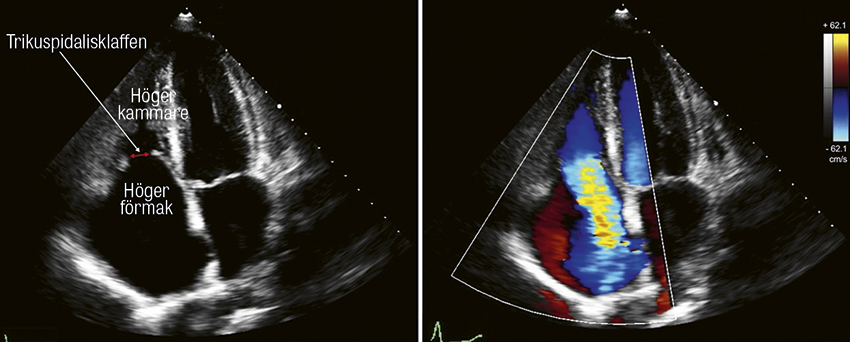

Översikt Kateterburna interventioner möjlighet för sköra patienter